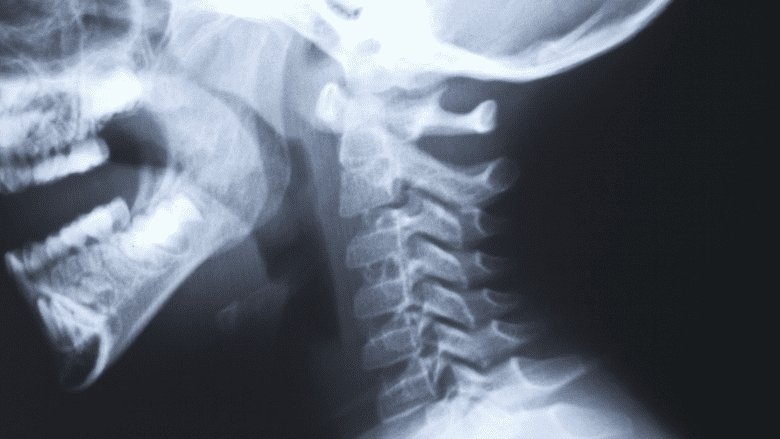

Occasionally, x-rays are used to help diagnose cervicogenic headaches.

Diagnostic imagery such as x-rays, computerized tomography (CT) scans, and magnetic resonance imaging (MRI) may only be used to support a diagnosis, but do not generally confirm the diagnosis in CGH. Cervical disc bulging as seen in these images may not always indicate the cause of CGH. This technique is more useful to identify causes such as tumors or birth defects.